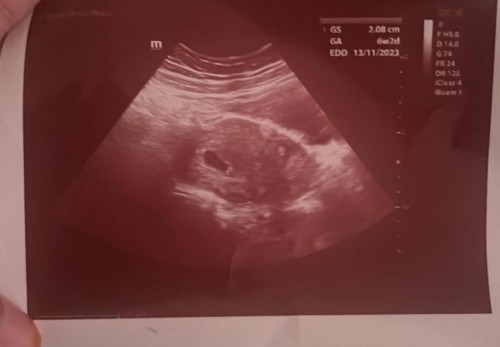

6weeks scan

hi moms. ada tk moms yg 6weeks scan tp tk nampak baby and heartbeat lg. cuma kantung je macam nj ?😅 #ingintahu #firstbaby #pleasehelp

sama dgn sye sis scan sis ni. sye pun ikutkn 6weeks 2nd baby.. masa anak first 7weeks+ ade heartbeat. tp yg ni 6week kantung je. doc kate sbb period irregular & penempelan lewat dr jangkaan sbb tu.. 2minggu lg sye akn scan lg.

saya scan waktu 6w nampak yolk sac tu jantung takde lagi. tadi repeat scan 8w alhamdulillah dah nampak jantung kelip kelip & dengar degupan jantung dia. kena repeat scan 2 minggu lagi inshaAllah dah boleh nampak jantung baby

update : harini scan dh nampak baby and jantung dia. ikut scan 7weeks4days. ikut LMP 8weeks 😅